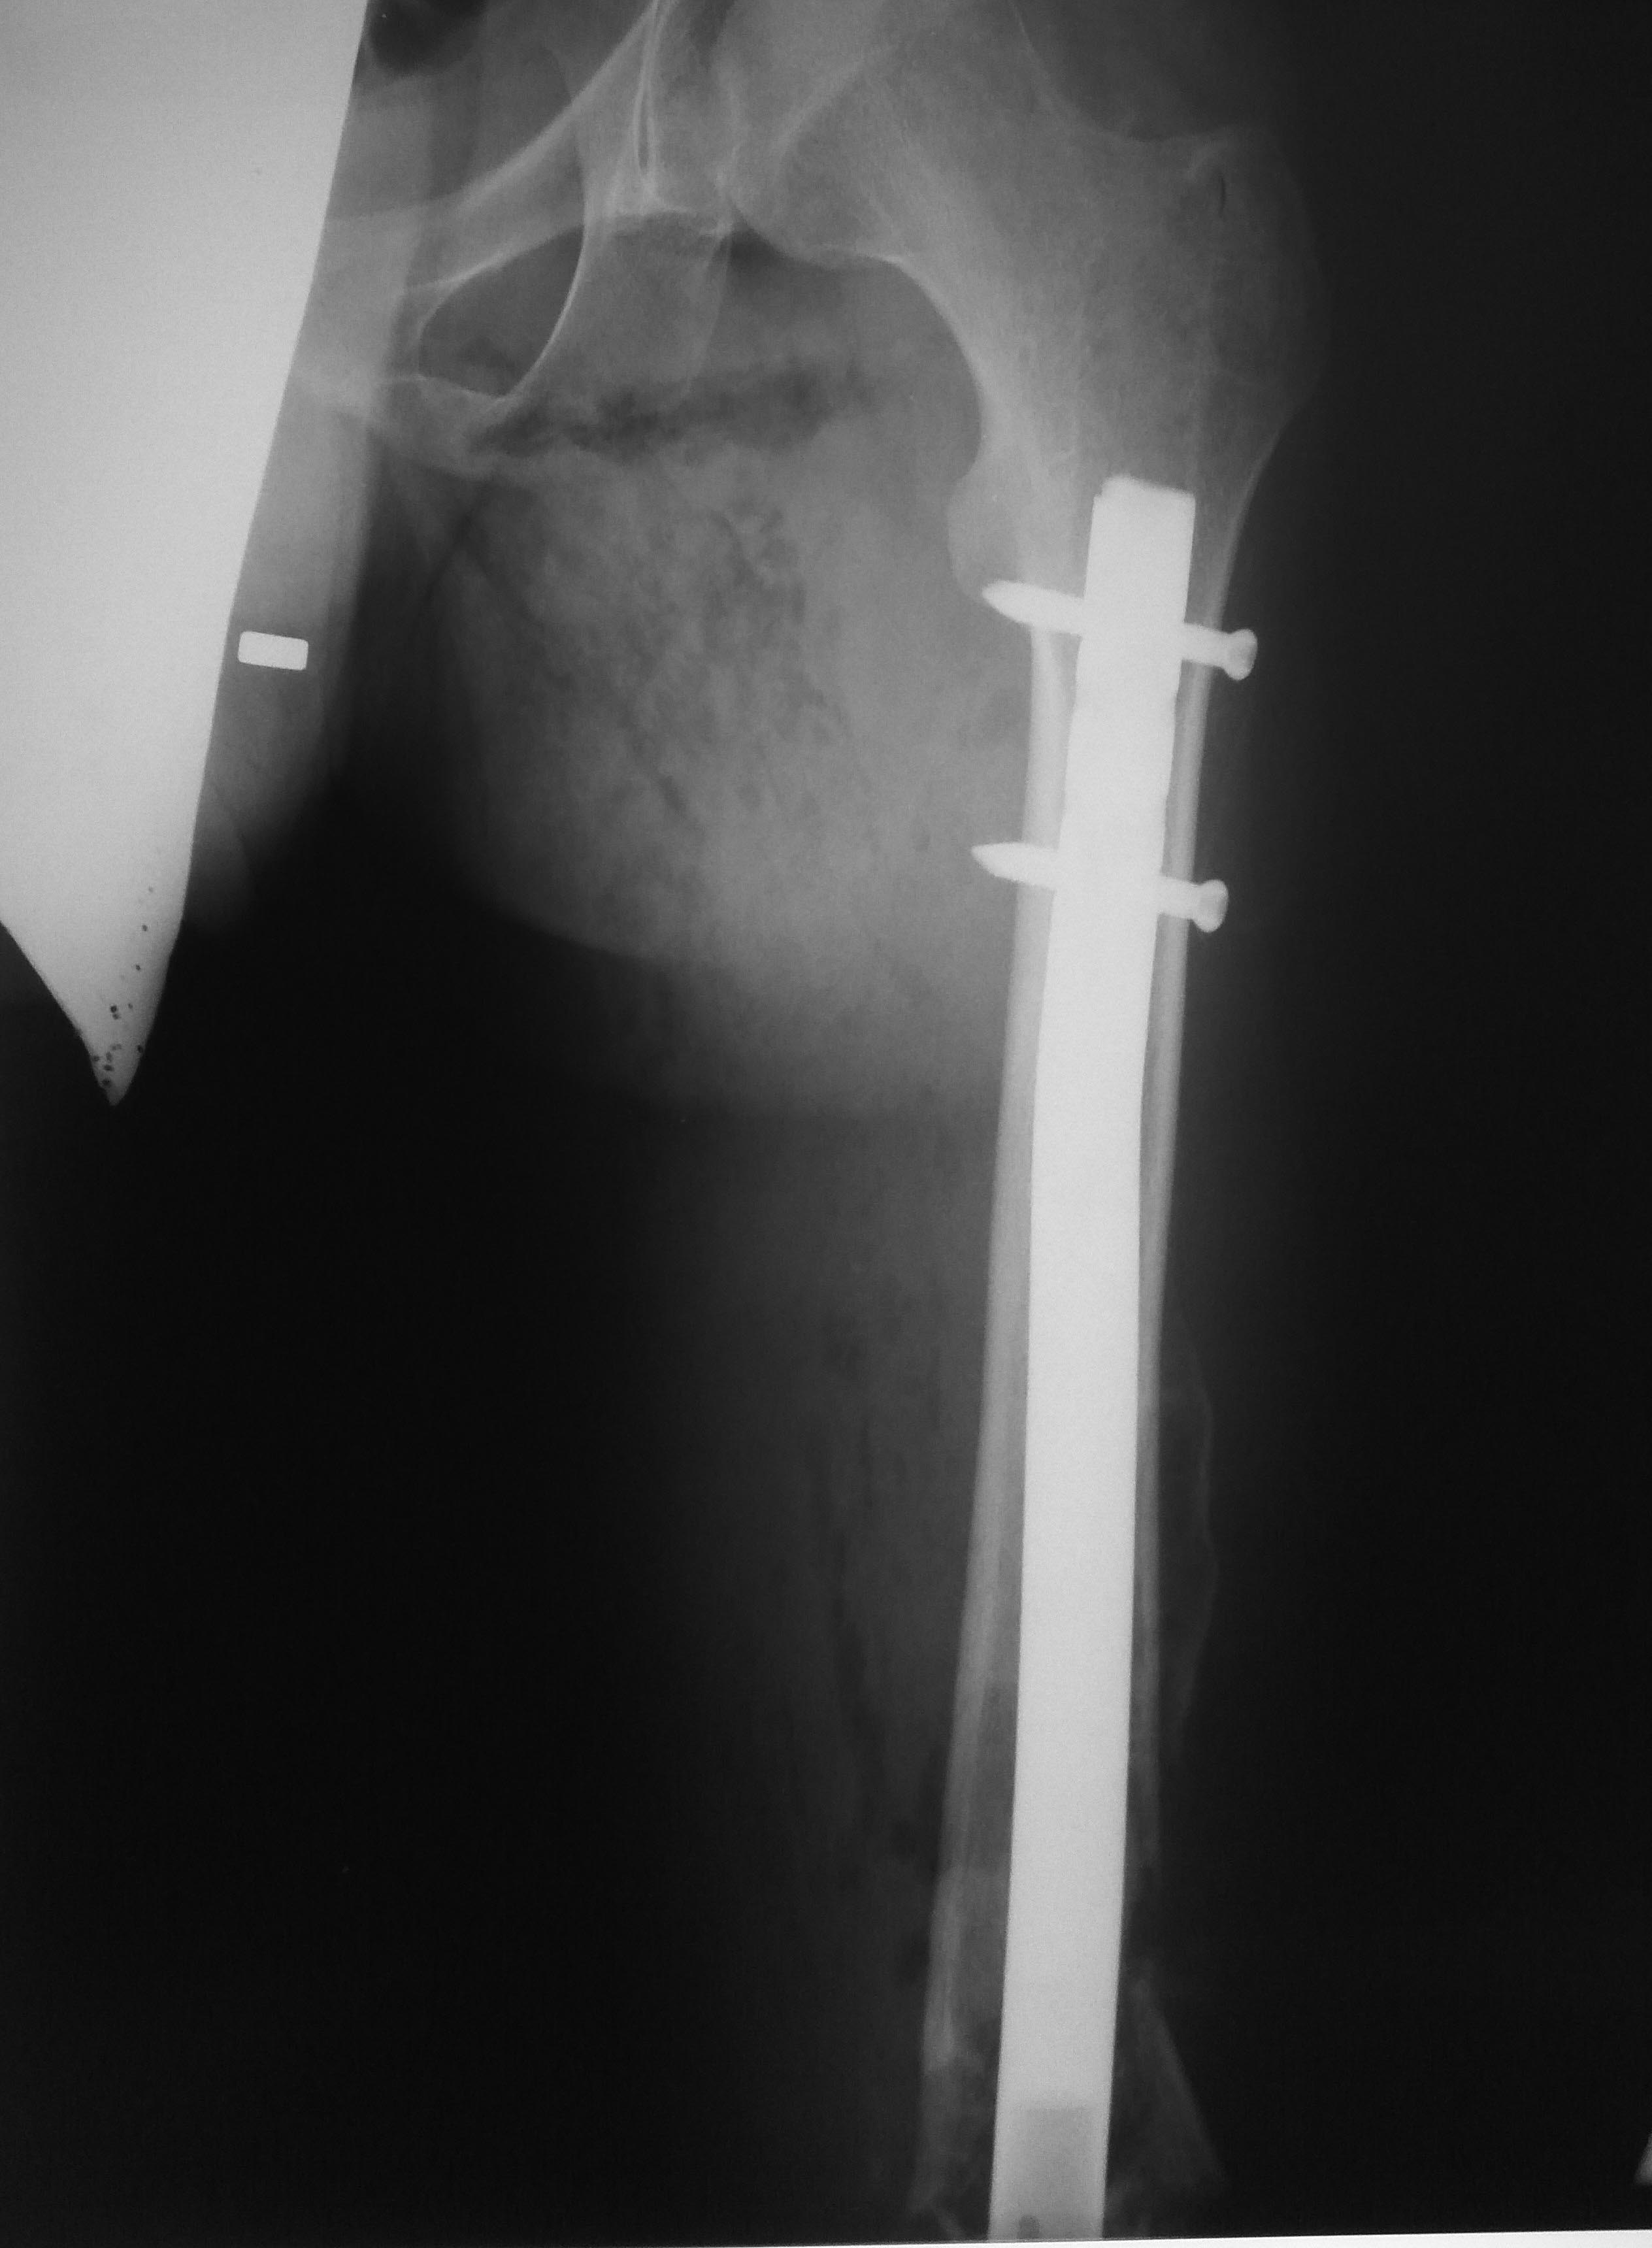

Оптимальное решение - закрытый остеосинтез интерамедуллярным стержнем с удлинением ножки эндопротеза. Пример в приложении. Делает такие стержни предприятие ЦИТО.

Все прошло по плану. Длину восстановили дистрактором. Пришлось сделать небольшую чрескожную остеотомию, чтобы устранить смещение по ширине.

Прежде всего от лица всего отделения травматологии и ортопедии Калужской областной детской больницы хочу выразить огромную благодарность Александру Николаевичу, который сначала откликнулся на нашу просьбу о помощи, на всём пути координировал процесс заказа и изготовления импланта и нашёл время приехать к нам в больницу помочь с этой непростой операцией. Опыт, приобретённый во время операции и общения с Вами - бесценен. Безо всякой лести.